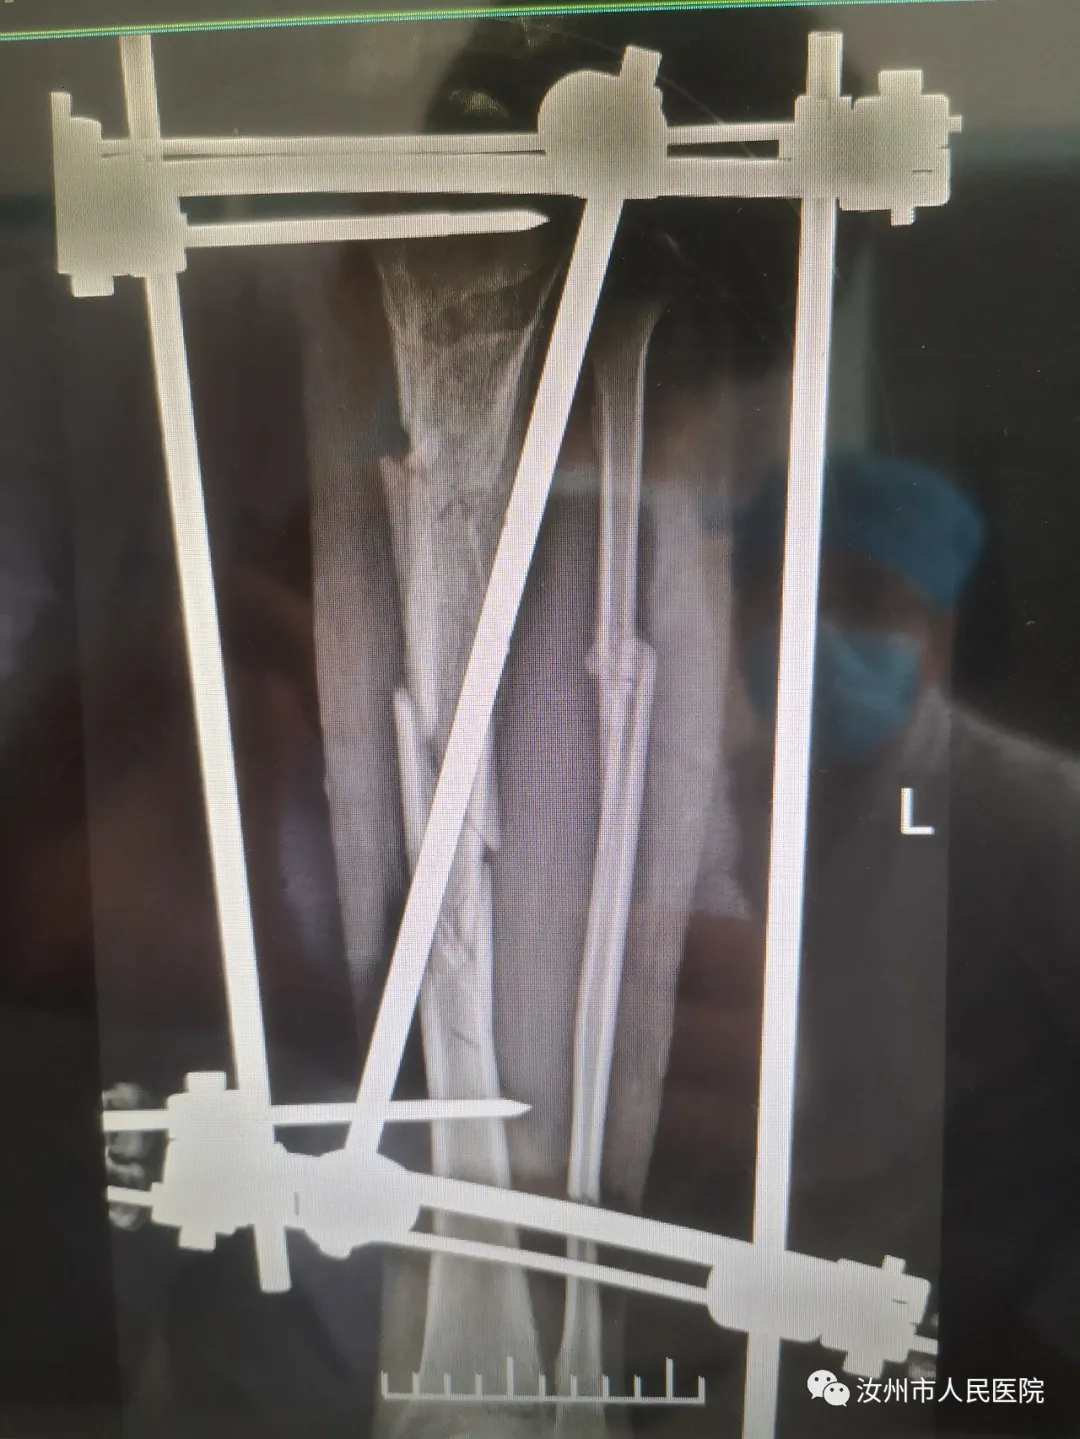

32岁的男性患者刘某因车祸致双下肢骨折,左侧多发性粉碎性骨折,给予外固定术后,右侧多发性骨折,给予内固定术后,待刘某病情稳定后,来康复科进行早期康复介入治疗。在康复治疗师李梦凡指导下进行关节被动运动、助力主动运动、负重抗阻运动。继而行患肢足趾伸屈、踝关节背伸、旋转运动,指导家属并协助病人从足跟开始做压力递减的小腿部肌肉挤压运动,循序渐进地进行踝关节的背伸、旋转运动,膝关节的屈曲抗阻运动,促进全身运动,增加患者对骨折的康复信心。